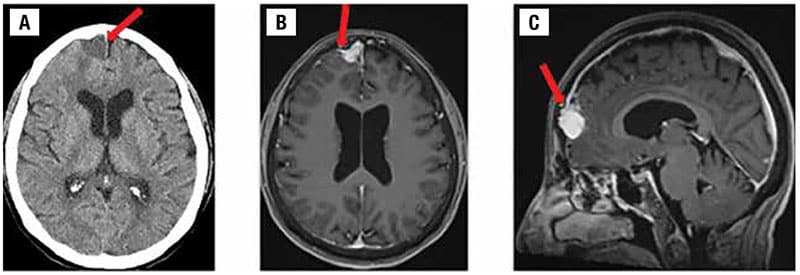

The patient underwent radiological assessment first with head CT scans without contrast, followed by MRI scans with and without contrast. The axial noncontrast head CT (Fig. 1A) demonstrated a homogeneous mildly hypodense 1.9-cm mass, resulting in mild impression upon the right frontal lobe with associated mild vasogenic edema. An associated small dural tail, which is similar to a meningioma, was denoted on an axial post-contrast T1-weighted brain MRI (Fig. 1B). This was also noted on sagittal post-contrast T1-weighted brain MRI (Fig. 1C).